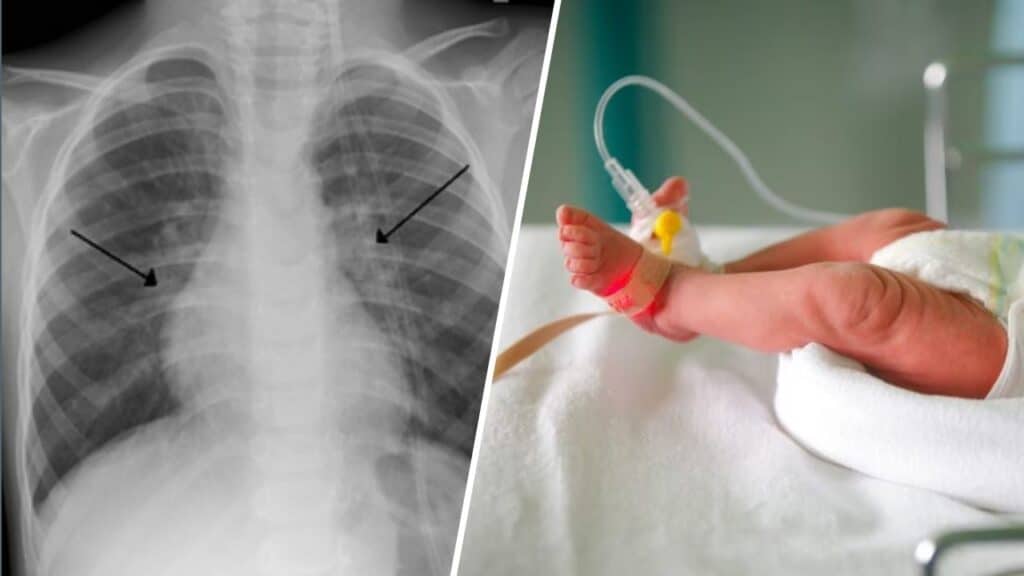

Picco di bronchiolite: muore bambina di 2 mesi, altri quattro in terapia intensiva. Una bambina di due mesi è morta all’ospedale di Desenzano del Garda, in provincia di Brescia. Il primo referto parla di bronchiolite, un’infezione alle vie respiratorie che sta avendo il suo picco in Italia in queste settimane.

La bambina, figlia di una coppia di origini romene residente in provincia di Mantova, era arrivata in ospedale in condizioni critiche ed è morta nel reparto di pediatria. Da giorni, la piccola accusava difficoltà respiratorie che sabato scorso sono peggiorate rapidamente. Sono in corso accertamenti per confermare la diagnosi dei medici del reparto.

Nel frattempo, quattro bambini, il più grande di poco meno di due anni, sono ricoverati in terapia intensiva neonatale all’ospedale “Moscati” di Avellino dopo essere stati infettati dalla bronchiolite. Due bambini sono stati trasferiti ad Avellino dal “Santobono” di Napoli, gli altri due provengono da centri della provincia irpina. I piccoli sono in assistenza respiratoria.